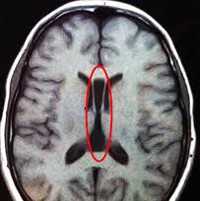

Одним из методов выявления пороков головного мозга у грудничков является нейросонография через родничок. Намного более точные данные у детей любого возраста и у взрослых получают при помощи МРТ головного мозга. МРТ позволяет определить характер и локализацию аномалии, размеры кист, гетеротопий и других аномальных участков, провести дифференциальную диагностику с гипоксическими, травматическими, опухолевыми, инфекционными поражениями мозга. Диагностика судорожного синдрома и подбор антиконвульсантной терапии осуществляется при помощи ЭЭГ, а также пролонгированного ЭЭГ-видеомониторинга. При наличии семейных случаев церебральных аномалий может быть полезна консультация генетика с проведением генеалогического исследования и ДНК-анализа. С целью выявления сочетанных аномалий проводится обследование соматических органов: УЗИ сердца, УЗИ брюшной полости, рентгенография органов грудной полости, УЗИ почек и пр.

Сделать это позволяет визуализация - инструментальная диагностика с помощью ультрасонографии.

Обнаруживается анэнцефалия на УЗИ - в виде дефекта открытой нервной трубки во время ультразвукового исследования плода на 12-й неделе беременности. При этом нередко наблюдается полигидрамнион (избыток околоплодных вод). Поэтому может быть необходим их анализ - амниоскопия и амниоцентез.

В дальнейшем, если беременность не прервалась самопроизвольно, в ходе УЗИ плода

дифференцируются анэнцефалия, микроцефалия, гидроцефалия плода, поскольку при микроцефалии череп недоразвит при наличии извилин, имеющих аномальную ширину. А в случае водянки головного мозга у новорожденного или врожденной гидроцефалии увеличен размер головы.